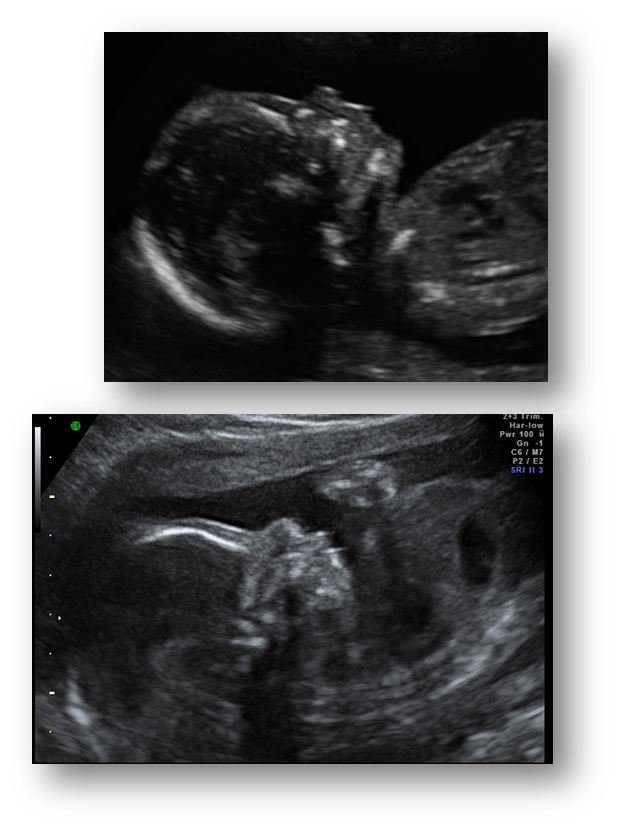

What are these images showing?

Nuchal Translucency